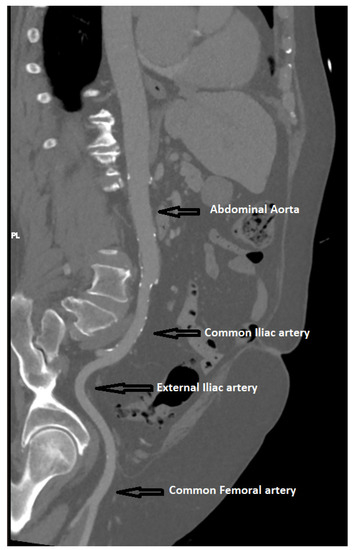

Measurements of peripheral arteries were performed using curvilinear reconstruction. After the curvilinear reconstruction, multiple axial sections were chosen at the operator’s discretion on the levels of the common iliac artery, external iliac artery, and common femoral artery, provided that the section was free of any significant lumen-narrowing atherosclerotic plaques (Figure 4).

Figure 4.

Measurement of peripheral arteries upon MDCT.